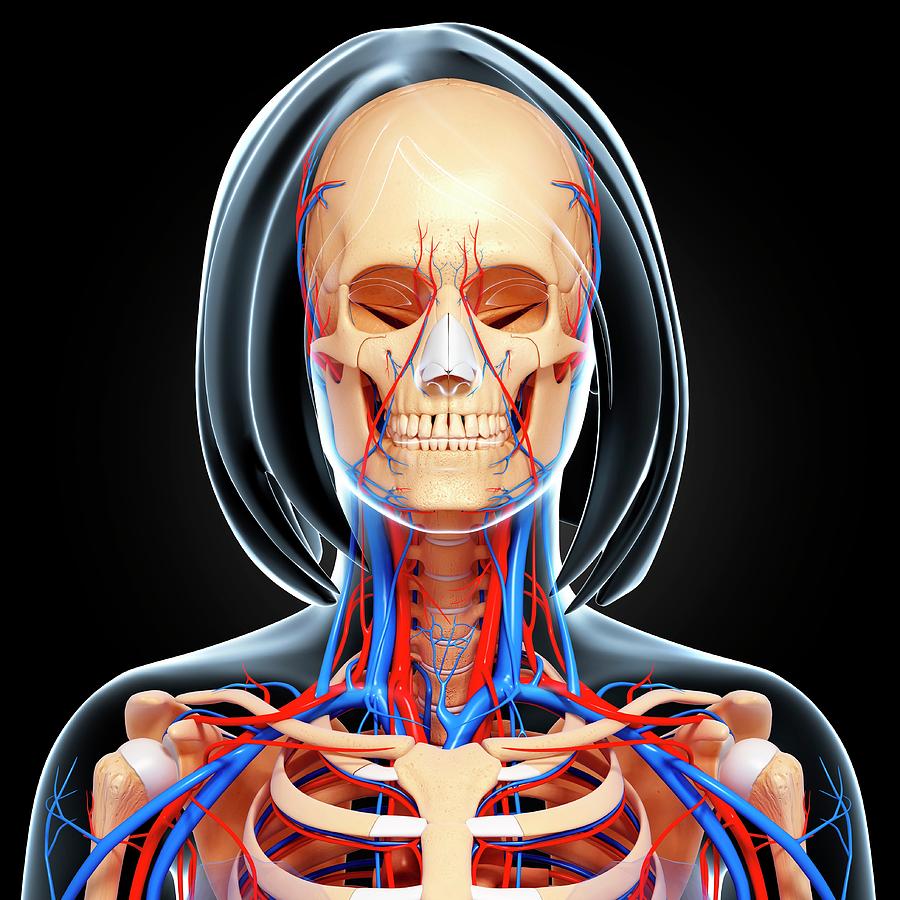

female anatomy art Complete female anatomy 3d model

fineartamerica.comFemale Anatomy, Artwork Stock Photo - Alamy

fineartamerica.comFemale Anatomy, Artwork Stock Photo - Alamy

fineartamerica.comFemale Anatomy, Artwork Stock Photo - Alamy

fineartamerica.comFemale Anatomy, Artwork Stock Photo - Alamy

www.alamy.comFemale Anatomy, Artwork Stock Photo - Alamy

www.alamy.comFemale Anatomy, Artwork Stock Photo - Alamy

bocadowasubo.github.ioFemale Anatomy, Artwork Stock Photo - Alamy

bocadowasubo.github.ioFemale Anatomy, Artwork Stock Photo - Alamy

fineartamerica.comFemale Anatomy, Artwork Stock Photo - Alamy

fineartamerica.comFemale Anatomy, Artwork Stock Photo - Alamy

www.etsy.comFemale Anatomy, Artwork Stock Photo - Alamy

www.etsy.comFemale Anatomy, Artwork Stock Photo - Alamy

www.alamy.comFemale Anatomy, Artwork Stock Photo - Alamy

www.alamy.comFemale Anatomy, Artwork Stock Photo - Alamy

www.alamy.comFemale Anatomy, Artwork Stock Photo - Alamy

www.alamy.comFemale Anatomy, Artwork Stock Photo - Alamy

fineartamerica.comFemale Anatomy, Artwork Stock Photo - Alamy

fineartamerica.comFemale Anatomy, Artwork Stock Photo - Alamy

Female Anatomy, Artwork Stock Photo - Alamy

www.alamy.comFemale Anatomy, Artwork Stock Photo - Alamy

www.alamy.comFemale Anatomy, Artwork Stock Photo - Alamy

www.etsy.comFemale Anatomy, Artwork Stock Photo - Alamy

www.etsy.comFemale Anatomy, Artwork Stock Photo - Alamy

www.alamy.comFemale Anatomy, Artwork Stock Photo - Alamy

www.alamy.comFemale Anatomy, Artwork Stock Photo - Alamy

www.alamy.comFemale Anatomy, Artwork Stock Photo - Alamy

www.alamy.comFemale Anatomy, Artwork Stock Photo - Alamy

Female Anatomy, Artwork Stock Photo - Alamy

www.alamy.com3d Rendered Illustration Of The Female Anatomy Stock Photo - Alamy

www.alamy.com3d Rendered Illustration Of The Female Anatomy Stock Photo - Alamy

fineartamerica.com3d Rendered Illustration Of The Female Anatomy Stock Photo - Alamy

fineartamerica.com3d Rendered Illustration Of The Female Anatomy Stock Photo - Alamy

pixels.comFemale Anatomy, Artwork Stock Photo - Alamy

pixels.comFemale Anatomy, Artwork Stock Photo - Alamy

www.alamy.comFemale anatomy art print women body torso drawing illustration modern. Female anatomy photograph by pixologicstudio/science photo library. Female anatomy, artwork stock photo

www.alamy.comFemale anatomy art print women body torso drawing illustration modern. Female anatomy photograph by pixologicstudio/science photo library. Female anatomy, artwork stock photo